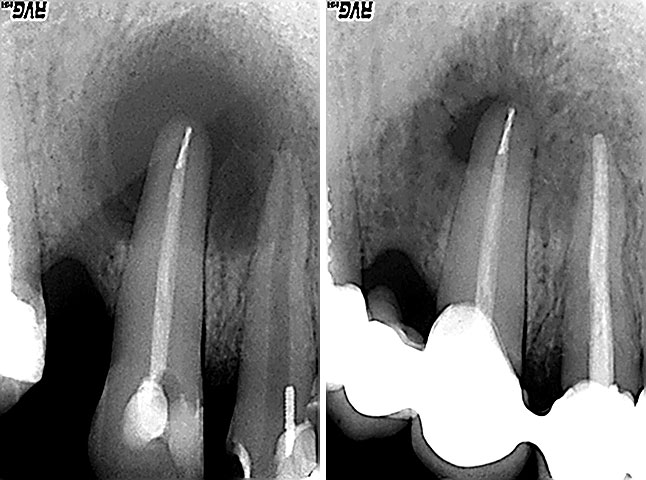

Endodoncija